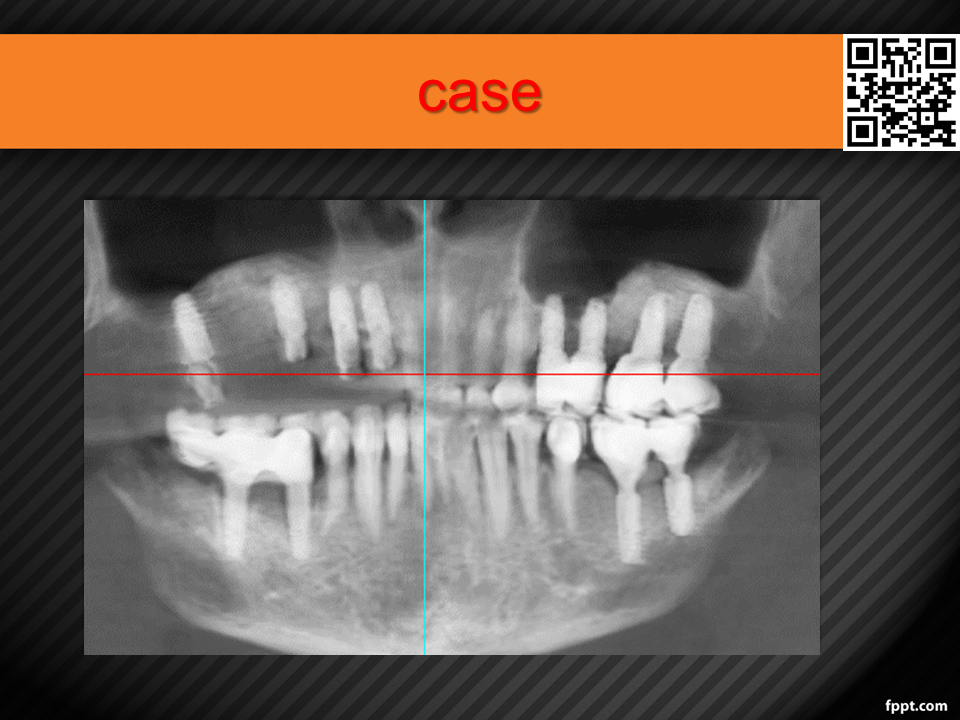

Vertical Alveolar Ridge Augmentation with 3D-Printed Titanium Mesh (30.10.2021)

Case report on vertical bone augmentation using a customized 3D-printed titanium mesh in a complex clinical scenario with prior implant failures. Includes surgical planning, techniques, complications, and an invitation for multicenter research collaboration. Presented by Dr. Levon Galstyan at AAOMFS.